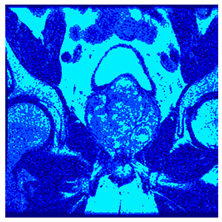

| Image | nt = 3 | nt = 4 | nt = 5 | nt = 8 |

|---|---|---|---|---|

| 1 | ![]() | ![]() | ![]() | ![]() |

| 2 | ![]() | ![]() | ![]() | ![]() |

| 3 | ![]() | ![]() | ![]() | ![]() |

| 4 | ![]() | ![]() | ![]() | ![]() |

| 5 | ![]() | ![]() | ![]() | ![]() |

| 6 | ![]() | ![]() | ![]() | ![]() |

| 7 | ![]() | ![]() | ![]() | ![]() |

| 8 | ![]() | ![]() | ![]() | ![]() |

| 9 | ![]() | ![]() | ![]() | ![]() |

| 10 | ![]() | ![]() | ![]() | ![]() |

| 11 | ![]() | ![]() | ![]() | ![]() |